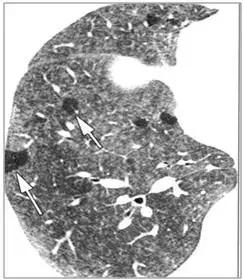

CT征象七:马赛克灌注

马赛克灌注(Mosaicperfusion)

在HRCT上,由于气道疾病或肺血管性疾病引起相邻的肺区血液灌注上的差别而出现的不均匀肺密度区,称马赛克/镶嵌性灌注。常见于造成局部气体滞留或肺实质通气不良疾病中 。

由于气体储留引起的马赛克灌注

小气道病变引起两侧肺的马赛克灌注

小气道病变引起两侧肺的气体潴留